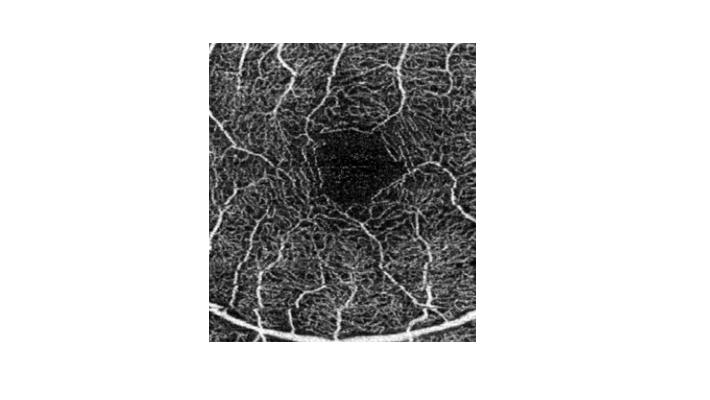

מדובר בבדיקה חדשנית אשר נמצאת בשימוש קליני בשנים האחרונות. הבדיקה מבוססת על תכנה מתקדמת אשר מבצעת 100,000 צילומים בשנייה אחת וכך מאפשרת לבחון בדיוק רב את זרימת הדם בנימים הפנימיים בעין [תמונות 5,6]. זוהי למעשה הבדיקה היחידה בגוף שמראה את בריאות הנימים הפנימיים בבדיקה שאינה פולשנית. תוצאות הבדיקה מספקות מידע חיוני על זרימת דם תקינה או חסרה, לרבות על היווצרות נימים חלשים שיכולים לדמם; על תגובת הנימים החולים לטיפולים; ועוד. הממצאים יכוונו להחלטות הטיפוליות. בדיקה זו כבר נעשית כיום במספר מחלקות עיניים בארץ ובמרפאות עיניים שונות.

בדיקת ה-OCT- Angio היא בעלת חשיבות רבה בחולי סוכרת ובעולם נחשבת כאחת מבדיקות השגרה כבר בשלבים הראשונים של המחלה, עוד לפני שנצפה נזק לרשתית בבדיקה קלינית ובבדיקת ה- OCT הרגילה. הממצאים בנימי הדם והשינויים או היציבות בהם עם הזמן יכולים להוסיף מידע תורם רב, כגון האם כבר נפגעו נימי-דם, ובמעקב לאורך זמן – האם הושגה יציבות בעזרת הטיפול הנוכחי או אולי חלה החמרה, ועוד.

במקרים אלה, בדיקת ה- OCT- Angio יכולה למשל להוכיח או לשלול את הימצאותם של נימים פתולוגיים ברשתית שגרמו להתפתחות הבצקת או לדימום גדול ברשתית. בנוסף, באמצעות ההדמיה ניתן ללמוד גם על נוכחות של נימים פתולוגים שאינם פעילים ('שקטים') בסוג היבש של המחלה, שעלולים לפתע לדלוף, לדמם ולהפוך את המחלה לרטובה.